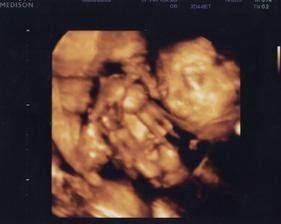

25.11. Na kontrole vše v pořádku. U ultrazvuku byl i budoucí tatínek a malý se náležitě předvedl. Vypadá to, že bude dělat Break dance 🙂 Má všechno, co mít má. Pan doktor nám sám od sebe ukázal i 3D UZ a vytiskl fotečku. Manžel sám od sebe jel nakoupit dětské oblečení a užíval si to málem více než já. Je krásné vidět, jak se na prcka těší. A viděli jsme camfrlika (výraz gynekologa) mezi nožkami 🙂